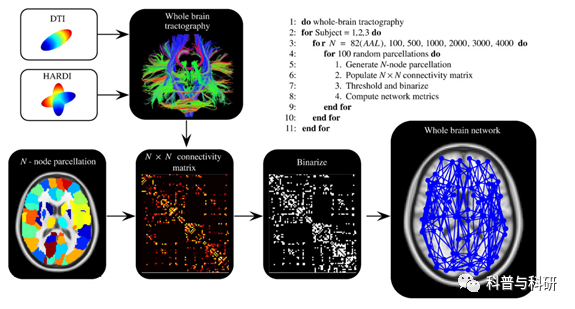

脑白质网络 构建 |

1、基于DTI数据的人脑连接组学方法学介绍 2、弥散磁共振数据的预处理 3、确定性纤维追踪脑网络构建 4、概率性纤维追踪脑网络构建 |

脑白质网络 拓扑计算 |

1、脑白质网络拓扑分析流程及参数介绍 2、脑白质网络拓扑分析上机操作 3、基于SurfStat的脑网络拓扑属性统计分析 |

网络属性统计 |

1、Rich-club属性统计分析 2、脑白质网络拓扑属性统计分析 3、基于NBS 连边统计分析 |

扩散成像处理实操 |

1、DTI基本原理、常用分析方法和预处理 2、TBSS数据批处理实现 3、TBSS数据分析实操以及结果呈现 4、其它DTI数据分析方法概述 |

基于ROI-ROI的确定性纤维追踪实现与统计 |

1、弥散张量成像的配准 2、ROI的空间转换 3、用TrackVis进行纤维追踪 4、纤维束的量化统计与结果展示 |

基于ROI-ROI的概率性纤维追踪预处理 |

1、概率性纤维束跟踪的模型构建 2、基于Volume的概率性纤维束跟踪实现 |

基于ROI-ROI的概率性纤维追踪统计 |

1、基于皮层的概率性纤维束跟踪实现 2、纤维束的量化统计与结果展示 |